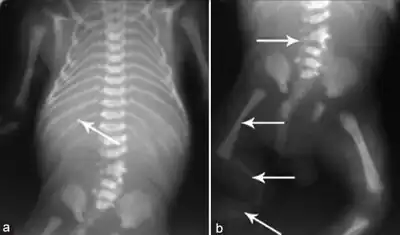

a) Hypoplastic mandible b)hypoplasia of right lower limb c) dilated urinary bladder asterisk and bilateral hydroureters arrowheads

a) Hypoplastic mandible b)hypoplasia of right lower limb c) dilated urinary bladder asterisk and bilateral hydroureters arrowheads -